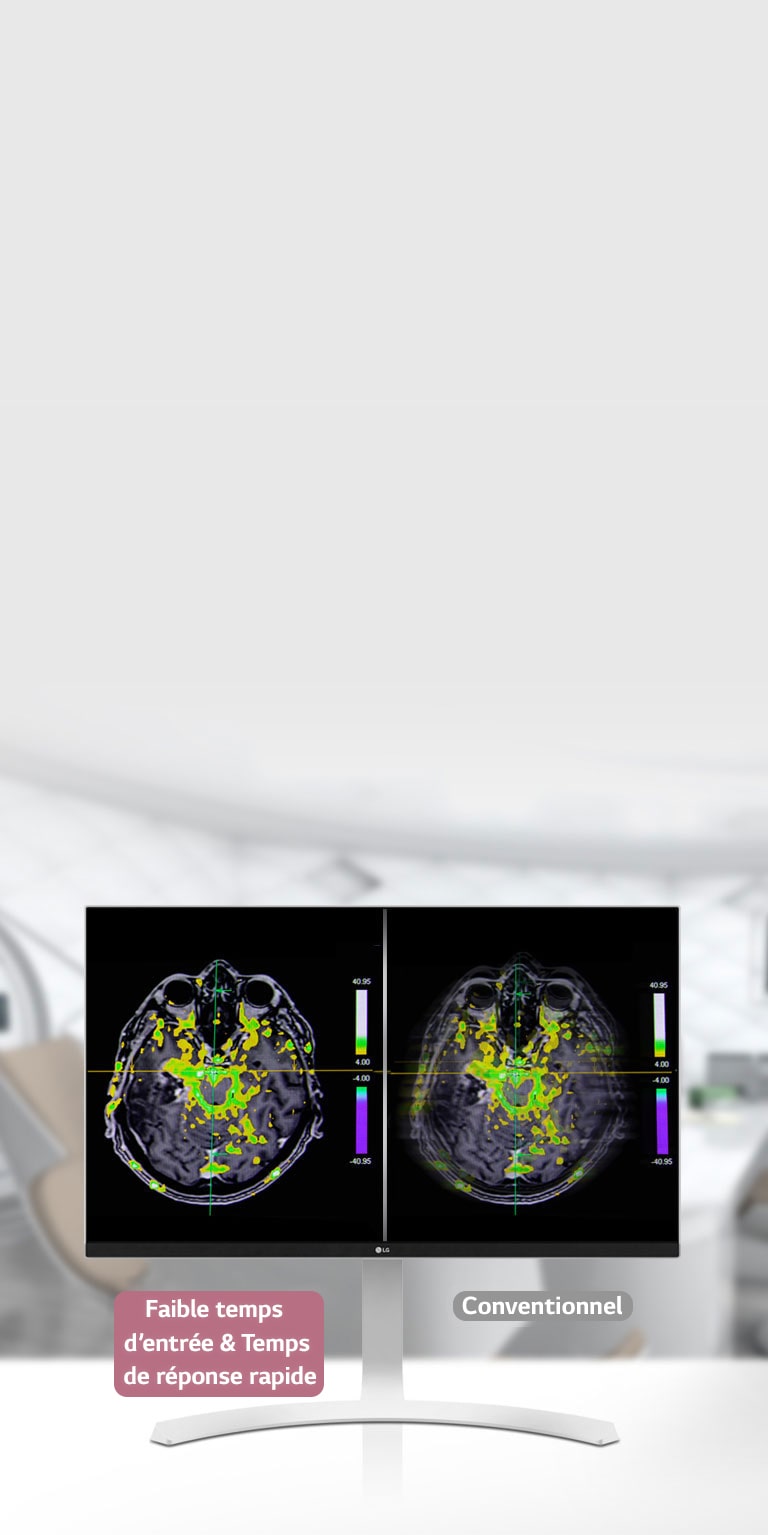

*Le Mode Dynamic Sync est uniquement disponible avec les sources d'entrée 60 Hz.

Temps de réponse

5ms (GtG - plus rapide)